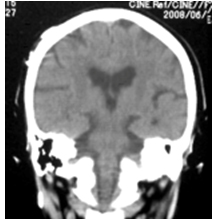

特発生正常圧水頭症のCT画像

特発生正常圧水頭症の特徴的CT所見(通常は脳を水平に撮影しますが、冠状に撮影した画像のほうがより特徴を捉えることができます)